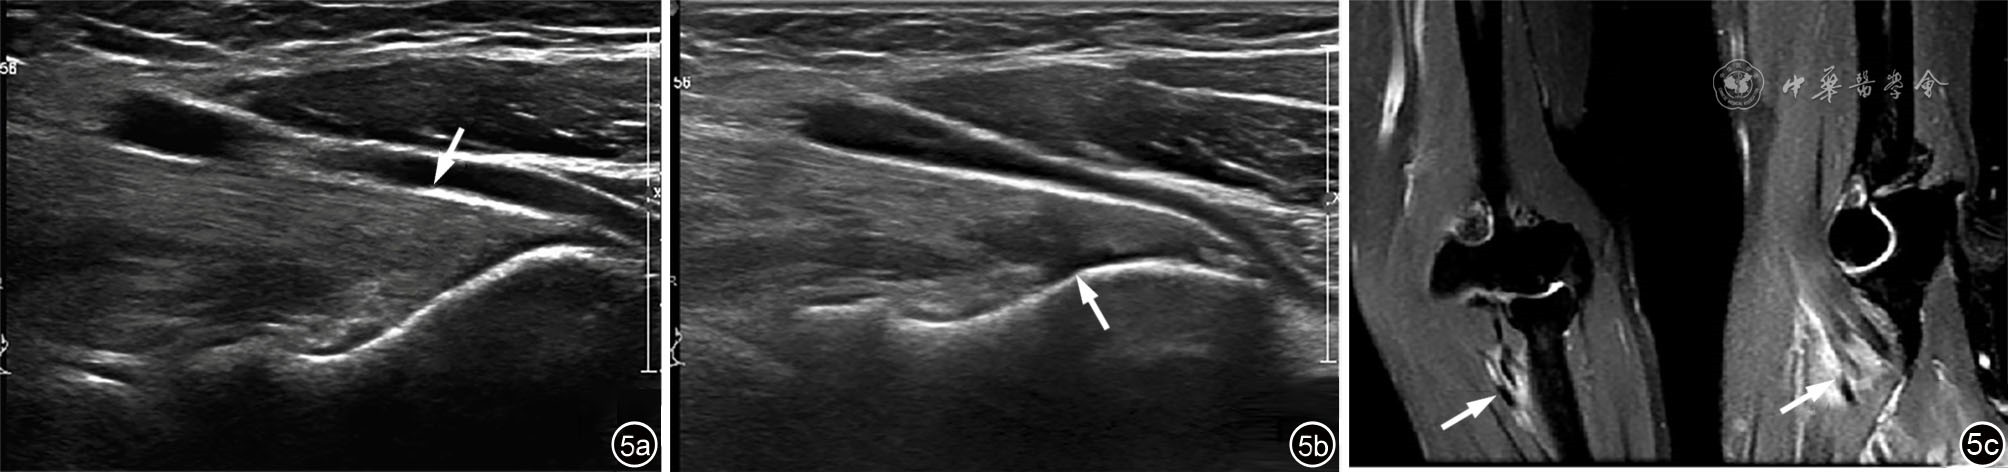

图5 患者女性,56岁,右侧肱二头肌远端肌腱Ⅱ级损伤(肌腱关节侧大部分撕裂但腱膜完好)超声及MRI图像。图a为常规超声探查显示肱二头肌远端肌腱稍肿胀,连续性及张力尚可(箭头所示);图b为抗阻力屈肘动态检查超声图像可显示关节侧损伤肌腱断端从桡骨粗隆附着端分离并可见局部积液(箭头所示);图c为MRI冠状及矢状面T2-FS序列显示肌腱肿胀,信号增高,肌腱附着端连续性大部分中断(箭头所示)